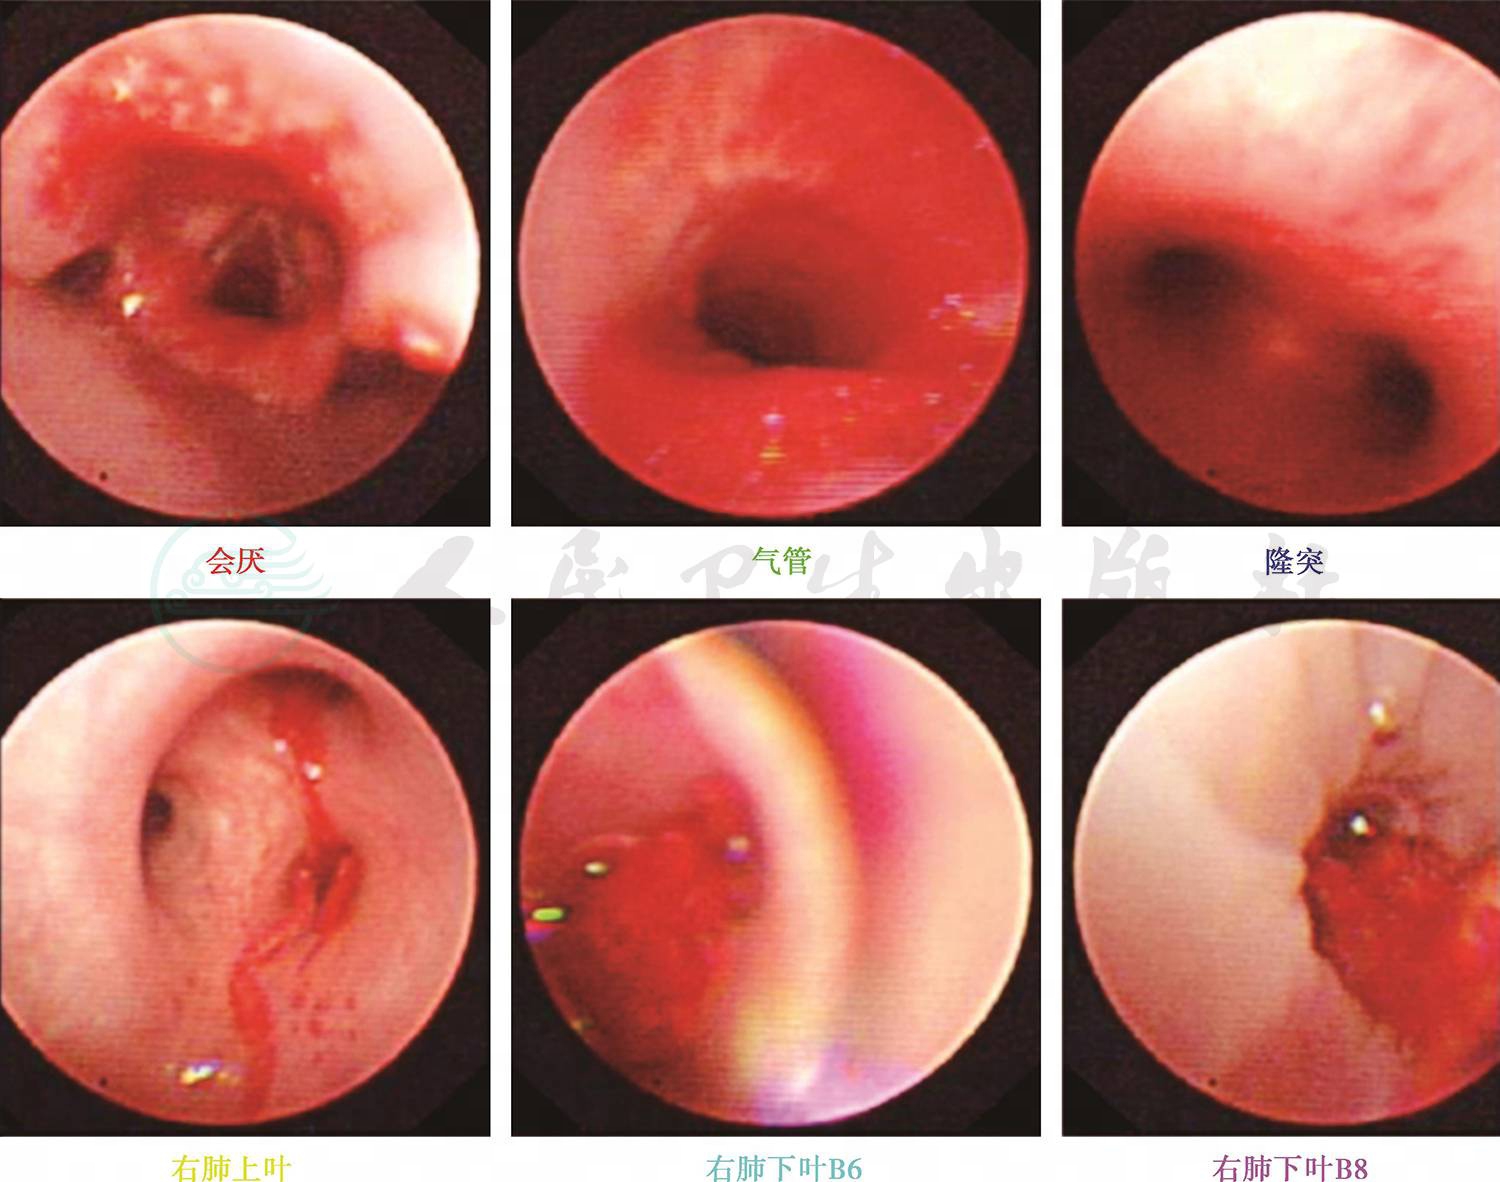

入院后急检血常规白细胞正常范围,予患儿头孢甲肟预防感染,同时完善病原学及相关常规检查。次日回报TB-Ab阴性;结核抗体阴性,肺炎衣原体抗体-IgM 阴性;肺炎支原体抗体-IgM 阴性,暂无结核、肺炎支原体及衣原体感染的证据;血红蛋白92g/L,提示轻度贫血。抗核抗体、抗nRNP抗体、抗Sm抗体、抗SS-A抗体、抗dsDNA抗体均阴性;抗线粒体抗体均为阴性;抗心磷脂抗体(ACA)、抗中性粒细胞胞质抗体测定(ANCA)及抗核抗体系列(ANA)均阴性,暂不支持系统性红斑狼疮等结缔组织病和ANCA相关性血管炎等引起的肺部损害。心电图正常,心脏超声正常不支持心源性咯血。入院第2天患儿再次咯血,量同前,检查血常规提示血红蛋白进行性下降提示肺部进行性出血,立即予患儿行支气管镜检查以明确出血部位,术中发现右肺下叶基底段可见鲜血涌出(图1),予1/10 000盐酸肾上腺素局部止血。因患儿出血量较大并急行肺部增强CT扫描提示:右肺中下叶见磨玻璃密度斑片影(图2),不除外肺血管异常导致出血,立即请介入科会诊,予患儿行支气管动脉造影术,术中发现血管略增粗扭曲,另见血管瘘(图3),予明胶海绵填塞后支气管动脉栓塞良好(图4)。夜间患儿再次出现呕血1次,约为50ml鲜血,患儿血氧饱和度下降,予患儿低流量吸氧,并予患儿垂体后叶素持续静脉滴注,联合凝血酶及酚磺乙胺止血并积极补液输血纠正贫血治疗。肺灌洗液结核菌涂片阴性,PPD阴性,结合支气管镜下的改变可除外肺结核;肺泡灌洗液未查到含铁血黄素细胞不支持肺含铁血黄素沉着症。患儿共住院治疗1周,无发热,未再次咯血及活动性出血表现出院观察。出院后电话随诊,患儿出院后无再次咯血,无反复感染及咳嗽史。

图1 右肺下叶基底段可见鲜血涌出